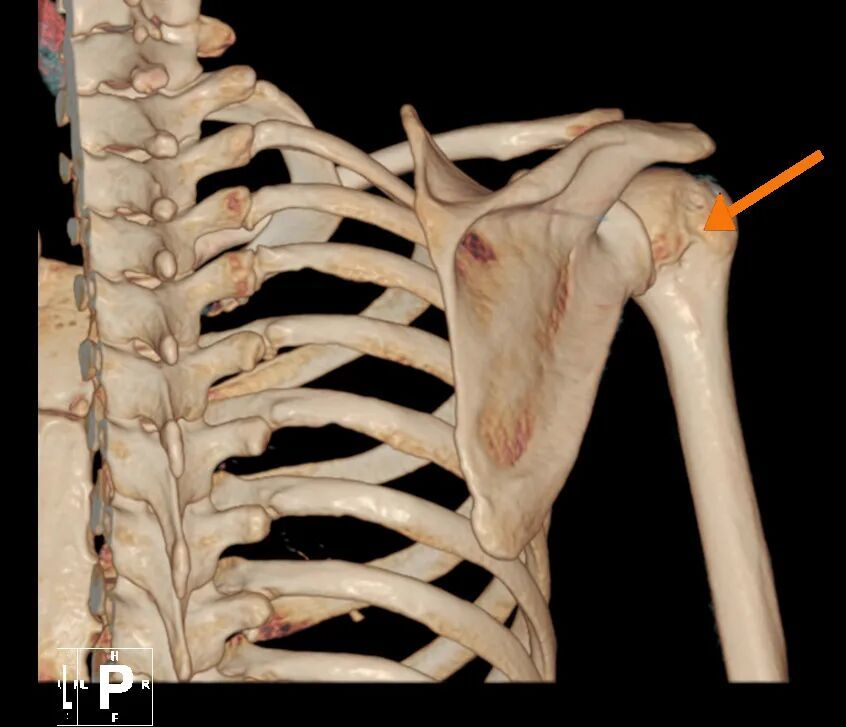

肱骨头骨缺损

针对林女士的病情,叶庭均与安亭医院骨科团队制定了关节镜微创手术方案。该手术仅需在肩部开数个不足1厘米的小切口,通过内置摄像头与精密器械精准修复受损部位,具有创伤小、恢复快的优势。手术中,医生发现其肩关节前盂唇存在明显撕裂,并伴有肱骨头骨缺损,随即进行了盂唇修复与关节囊固定术,重建了肩关节稳定性。术后,林女士在骨科团队指导下逐步进行康复训练,肩关节功能恢复顺利,目前已重返日常生活。